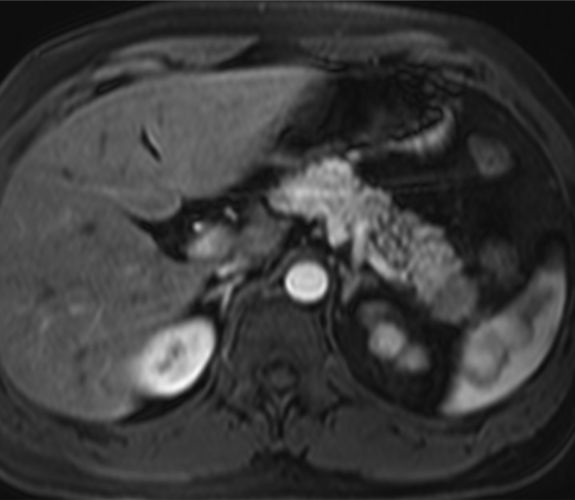

Hombre de 39 años con antecedente de fibrosis retroperitoneal.

Se solicita TC porque en RM externa realizada para control de la fibrosis retroperitoneal se informa de sospecha de neoplasia de cola de páncreas.

3. ¿Cuál es tu diagnóstico?

- A. Tumor pseudopapilar sólido pancreático con metástasis renales izquierdas.

- B. Linfoma pancreático -forma localizada- y lesiones atróficas renales izquierdas secundarias a fibrosis retroperitoneal.

- C. Lesión metastásica en páncreas de tumor primario renal.

- D. Pancreatitis autoinmune en contexto de enfermedad relacionada con la IgG4.

- E. Sarcoidosis con afectación pancreática y renal.